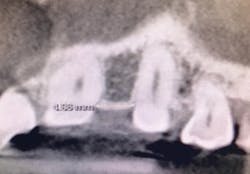

A 50-year-old female presented with a missing tooth No. 12 that was extracted for unknown reasons more than 10 years ago (figure 7). The patient was referred to our office for an implant consultation. Upon review of a CT scan, it was revealed that at the widest area buccal-lingually there was 4.09 mm and at the narrowest 3.8 mm (figure 8). She was presented with two treatment options: bone grafting or a narrow-diameter implant. She opted for the narrow-diameter implant, as it eased several of her concerns: she was unhappy with a removable appliance, worried about a block graft for a single tooth, and finances were a burden.

Figure 8: Pre-op CT scan